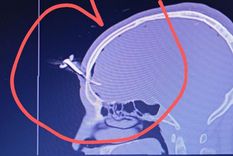

llave

Le clavaron una llave en la cabeza durante una feroz pelea y hubo shock en un partido juvenil